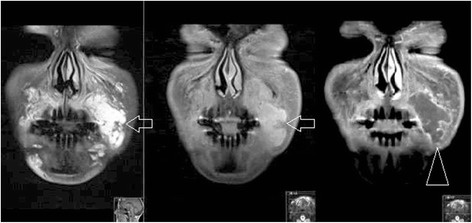

Поэтому, когда у людей, делавших уколы красоты десять лет назад, МРТ показывало, что наполнители все еще там, это неудивительно. Особенно это заметно в области вокруг глаз. Другие исследования нашли наполнители, введенные 2, 6 и 12 лет назад. Причем испытуемые отрицали, что когда-либо их делали, пока им не показали снимки, где наполнители все так же были на своих местах. Самое интересное — это то, что наполнители могут перемещаться.

Также стоит помнить, что срок жизни природной гиалуроновой кислоты, создаваемой вашим телом, намного меньше, чем коммерческой. Компании изменяют ее, делая кислоту более прочной и долговечной, чтобы она дольше хранилась на полке и медленнее распадалась в теле. Если вы видели лица людей, которых как будто пчелы покусали после уколов гиалуронки, так это от того, что они считают, что их наполнитель закончился, и им нужно вводить еще. Однако, как мы уже усвоили, никуда он не исчез, а просто переместился, что и приводит к провисанию кожи, искажению лица и возможным медицинским осложнениям.

Di Girolamo, Marco, et al. "MRI in the evaluation of facial dermal fillers in normal and complicated cases." European radiology 25 (2015): 1431-1442.

Mundada, Pravin, et al. "Injectable facial fillers: imaging features, complications, and diagnostic pitfalls at MRI and PET CT." Insights into imaging 8 (2017): 557-572.

Master, Mobin. "Hyaluronic acid filler longevity and localization: magnetic resonance imaging evidence." Plastic and Reconstructive Surgery 147.1 (2021): 50e-53e.

Tal, Sigal, et al. "MRI in detecting facial cosmetic injectable fillers." Head & face medicine 12 (2016): 1-7.